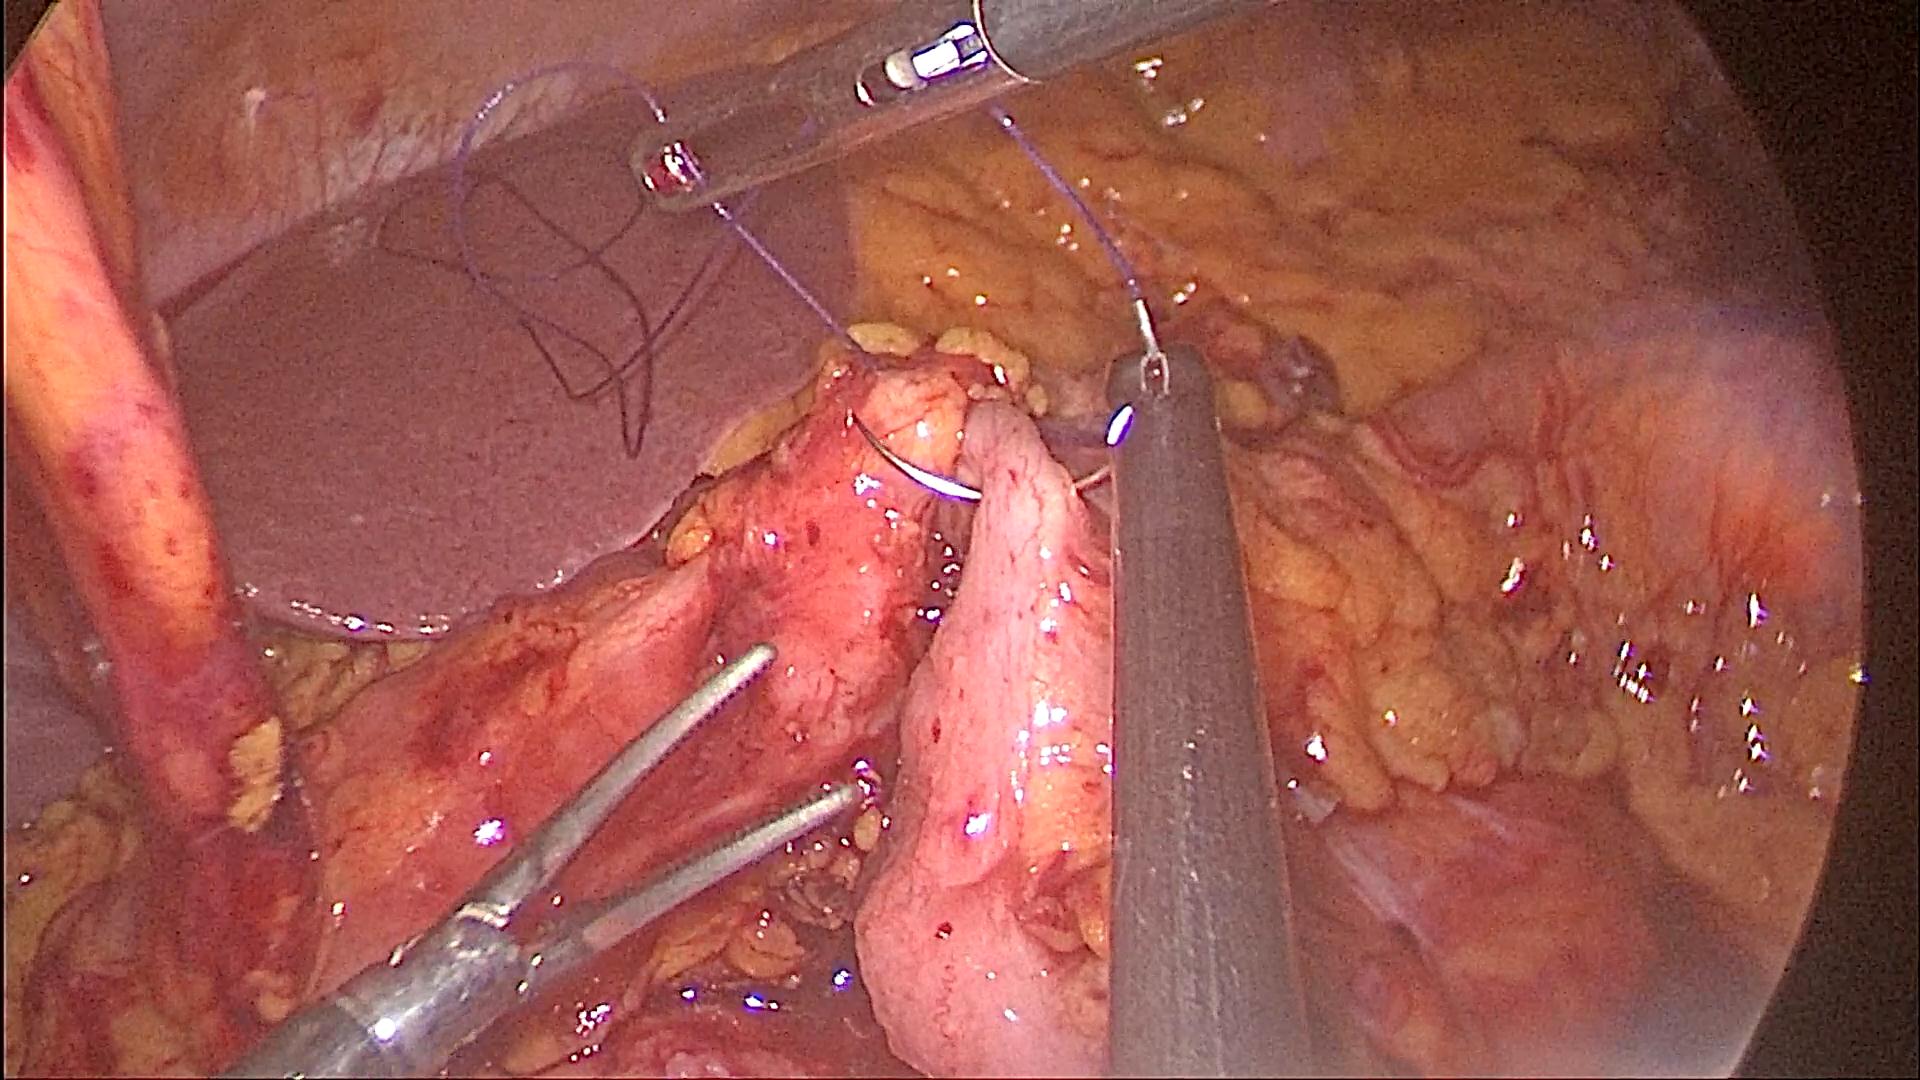

Phẫu thuật nội soi hoàn toàn cắt cực trên dạ dày, miệng nối thực quản – dạ dày được thực hiện bằng tay (BN Hoàng Thị H)

91 tuổi, phát hiện bị ung thư dạ dày và sức khỏe lại không được tốt, các con của bà Hoàng Thị K dự định chọn giải pháp chăm sóc giảm nhẹ để bà bình an đi nốt con đường chứ không muốn phẫu thuật vì sợ bà phải chịu thêm đau đớn. Tuy nhiên, khi xin ý kiến mẹ mình, thì bà K lại bảo: Mẹ xem tivi, nghe đài, đọc báo nhiều nên biết Bệnh viện Bạch Mai đang áp dụng nhiều kĩ thuật tiên tiến trong phẫu thuật và đã cứu sống được rất nhiều người mắc bệnh hiểm nghèo. Thể theo nguyện vọng của mẹ, ông Ngô Thanh S (con trai bệnh nhân) đã đưa mẹ đến khám tại Trung tâm Tiêu hóa – Gan mật, Bệnh viện Bạch Mai. Sau khi nội soi, chụp chiếu và làm các xét nghiệm cận lâm sàng cần thiết, bà được chuyển sang Khoa Phẫu thuật Tiêu hóa – Gan mật tụy. Tại đây, các bác sĩ nhận định bệnh nhân K có chỉ định phẫu thuật nội soi cắt đoạn dạ dày, nạo vét hạch. Với sự giúp sức của Trung tâm Gây mê và Hồi sức ngoại khoa, qua 5 lỗ nhỏ trên thành bụng, kích thước từ 0,5 đến 1 cm, các phẫu thuật viên của Khoa phẫu thuật Tiêu hóa – Gan mật tụy đã đưa camera và các dụng cụ nội soi tiếp cận, phẫu tích, bóc tách dạ dày và các mạch máu, hạch liên quan.